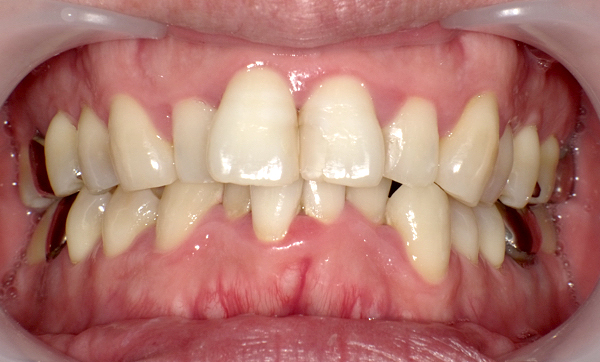

症例_008 「上下の前歯」症例

治療期間:13ヶ月金額:57万円+税40代女性捻転歯前歯のガタガタ

Before | After |